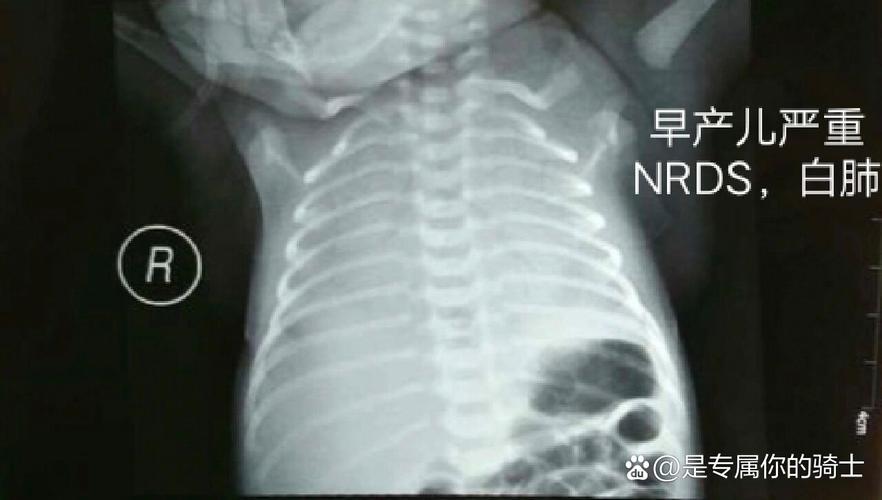

- 肺部问题: 这是新生儿X光最常用的目的,用于诊断新生儿肺炎、肺透明膜病(RDS)、吸入综合征(如羊水吸入、胎粪吸入)、气胸、肺不张等,这些疾病可能危及生命,及时准确的诊断是治疗的关键。